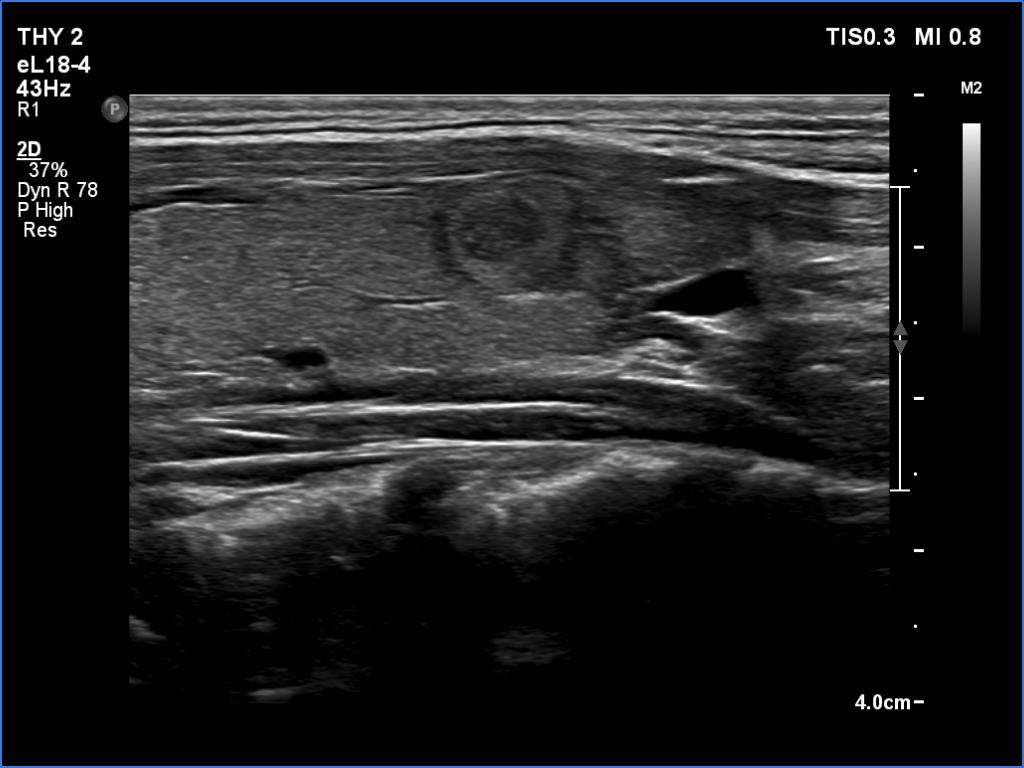

Right lobe, transverse scan

Right lobe, longitudinal scan

This is the usual course of Graves' disease regarding the change in echo pattern - before, during and after the activity of the autoimmune process. The only exception is the change in the size of the thyroid. In most cases, the thyroid increases during the activity of the disease, then returns to normal. However, in this patient the age counts: at the first examination, the patient was only 15-year-old.